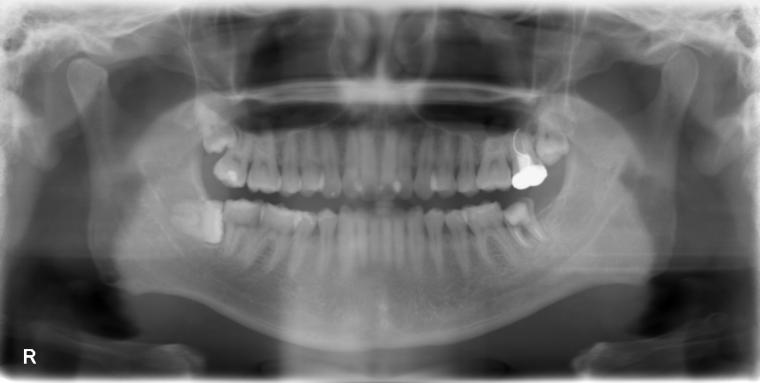

下顎大臼歯1本欠損症例

31歳男性/下1本欠損/インプラント埋込手術

左下第二大臼歯が、残根の状態でご来院された患者さんです。

抜歯後に土台となる骨をつくる処置の後、インプラントを埋入しました。